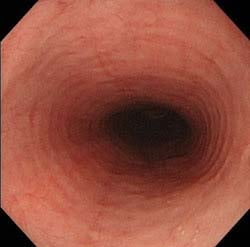

胸やけや食べ物のつまり感などを訴えられ、逆流性食道炎を疑って胃カメラ検査を行うと、逆流性食道炎ではない特殊な食道炎であることがしばしばあります。好酸球性食道炎は何らかのアレルギーが原因で起こる食道炎で特徴的な内視鏡所見を認めます。厚生労働省の指定難病の一つです。またカンジダ性食道炎はカビの一種であるカンジダが食道粘膜に付着することで、胸やけを起こします。こちらも特徴的な内視鏡所見を示します。

<食道カンジダ症>

白い酒粕のようなものがカンジダです。少量のカンジダが付着している食道は珍しくなく、自覚症状はありません。 -

好酸球性食道炎もカンジダ性食道炎も胸痛、胸やけ、嚥下障害、食物のつかえ、腹痛などが主な症状です。逆流性食道炎と症状は同じです。好酸球性食道炎は好酸球性胃腸炎を合併することもあり、その場合は腹痛や下痢などが合併することもあります。ただし、好酸球性食道炎は特徴的な内視鏡所見だけを示して、無症状の場合もあります。また、同様にカンジダが少量しか付着せず全く症状のない、食道カンジダ症という状態もあります。

| カンジダ性食道炎 | 食道にカンジダという真菌が付着して起こります。内視鏡検査でカンジダが付着する食道を観察することは珍しくありません。少量付着する程度であれば症状はありません。ただ免疫が低下した状態、癌患者やHIV感染者、糖尿病や高齢者になると食道粘膜に付着するカンジダが増えて症状を起こすようになります。 |

| カンジダ性食道炎 | 全く症状がなく少量のカンジダが付着する程度の食道カンジダ症であれば治療は必要ありませんが、カンジダが食道に多く付着し症状がでているカンジダ性食道炎であれば抗真菌薬の内服を行うとともに、免疫力が低下している原因を治療していきます。 |

| カンジダ性食道炎 | 免疫が低下しないために、疲れないようにすることは重要です。糖尿病などの基礎疾患がある方は、基礎疾患のケアが重要です。 |